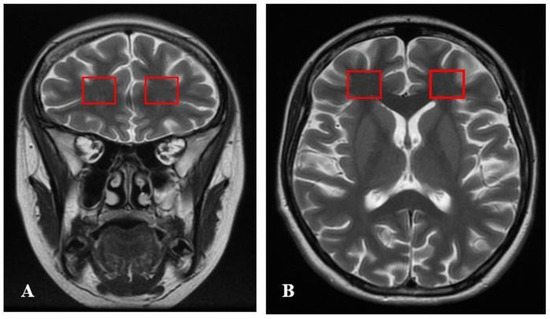

2.1. Clinical Characteristics of Schizophrenia Patients

2.4. MR Spectroscopy and Laboratory Measurements

4.6. Neuroimaging Analysis